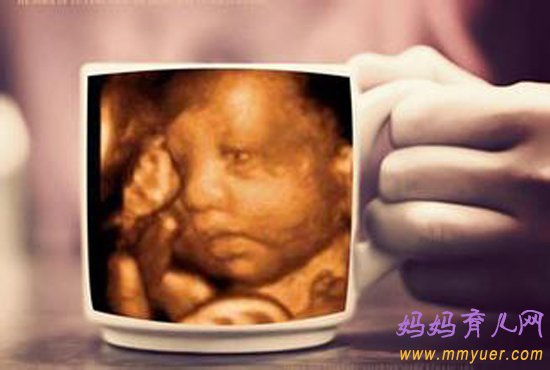

四维彩超是超声检查的一种,除了一般彩超的功能外,还可以进行胎儿头面部立体成像,可清晰地显示眼、鼻、口、下颔等状态,可协助医生直接对胎儿先天畸形进行诊断,包括表面畸形、内脏畸形和头面部畸形,能确定胎儿在子宫中的精确位置。此外,四维彩超还在这些功能的基础上加上时间维度参数,可以实时观察胎儿动态的活动图像。

四维彩超什么时候做最好?一般来说,怀孕24-28周是照四维彩超的最佳时间,因为胎儿24周左右正是大脑突飞猛进的发育时期,这个时期的胎儿结构已经形成,胎儿的大小以及羊水适中,在宫内的活动空间较大,胎儿骨骼回声影响比较小,图像也比较清晰。

四维超声在三维超声的基础上有了实时动态的效果,准爸爸、准妈妈可以通过屏幕亲眼目睹宝宝在妈妈肚子里运动、呼吸、吞咽、打哈欠、伸舌头等生理活动,非常直观。